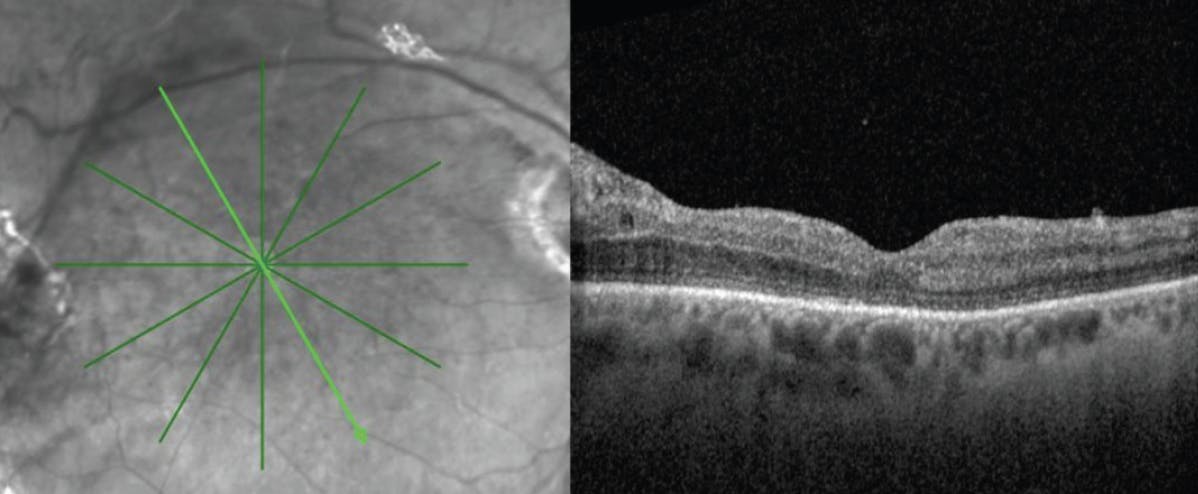

Four months postoperatively, the right eye had an attached macula under silicone oil with increased retinal thickness (Figure 2). The patient’s final VA was 20/400 OD.

<p>Figure 2. OCT imaging 4 months postoperatively showed an attached macula under silicone oil with increased retinal thickness.</p>

Figure 2. OCT imaging 4 months postoperatively showed an attached macula under silicone oil with increased retinal thickness.